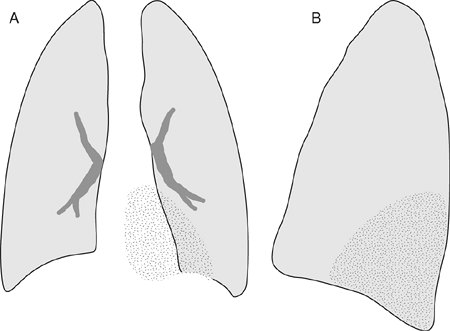

FIGURE 11-16. Left upper lobe atelectasis. A: Frontal view of the chest shows loss of the left heart border, elevation of the left hemidiaphragm, and increased opacification of the left lung (stippled area). B: Lateral view shows anterior displacement of the major fissure and increased retrosternal opacification (black area). (Reprinted with permission from

Collins J. Joseph E. Whitley, MD, Award. Evaluation of an introductory course in chest radiology. Acad Radiol. 1996;3:994–999.

)